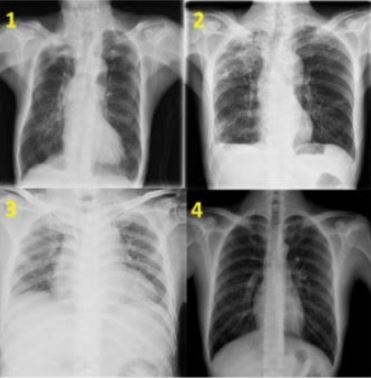

A equipe da Ufla desenvolveu um sistema de IA que pode analisar imagens de raios-X de pulmão (foto 1) para apoiar a triagem de tuberculose ativa. O mais inovador é que o diagnóstico preliminar pode ser feito a partir de uma simples foto da imagem tirada com um celular, agilizando o atendimento de uma doença que registrou cerca de 80 mil novos casos no Brasil em 2023.

Em parceria com Epamig e Embrapa, a Ufla desenvolve um modelo de IA capaz de identificar doenças e pragas no cafezal (foto 3) a partir de uma foto feita com smartphone. Minas Gerais é o maior produtor de café do Brasil, respondendo por 52,7% da produção nacional.